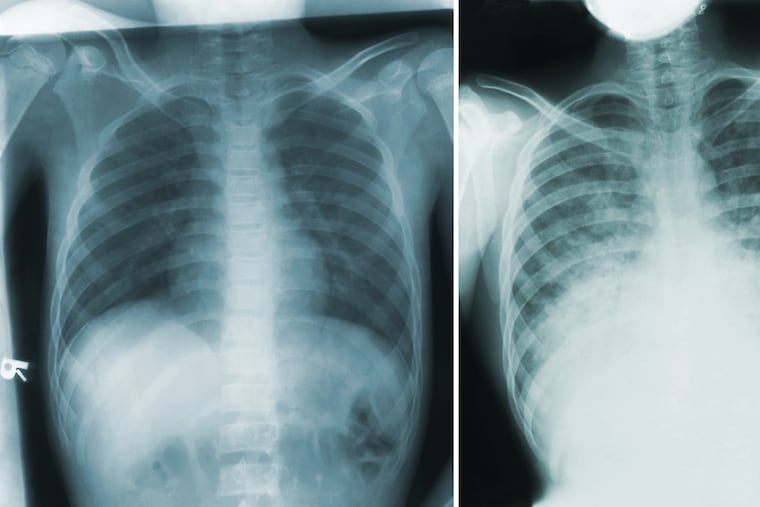

But these are not necessarily present for the pneumonic plague. Patients develop fever, headache, weakness, and a rapidly developing pneumonia with shortness of breath, chest pain, cough, and sometimes bloody or watery mucus, according to the CDC.